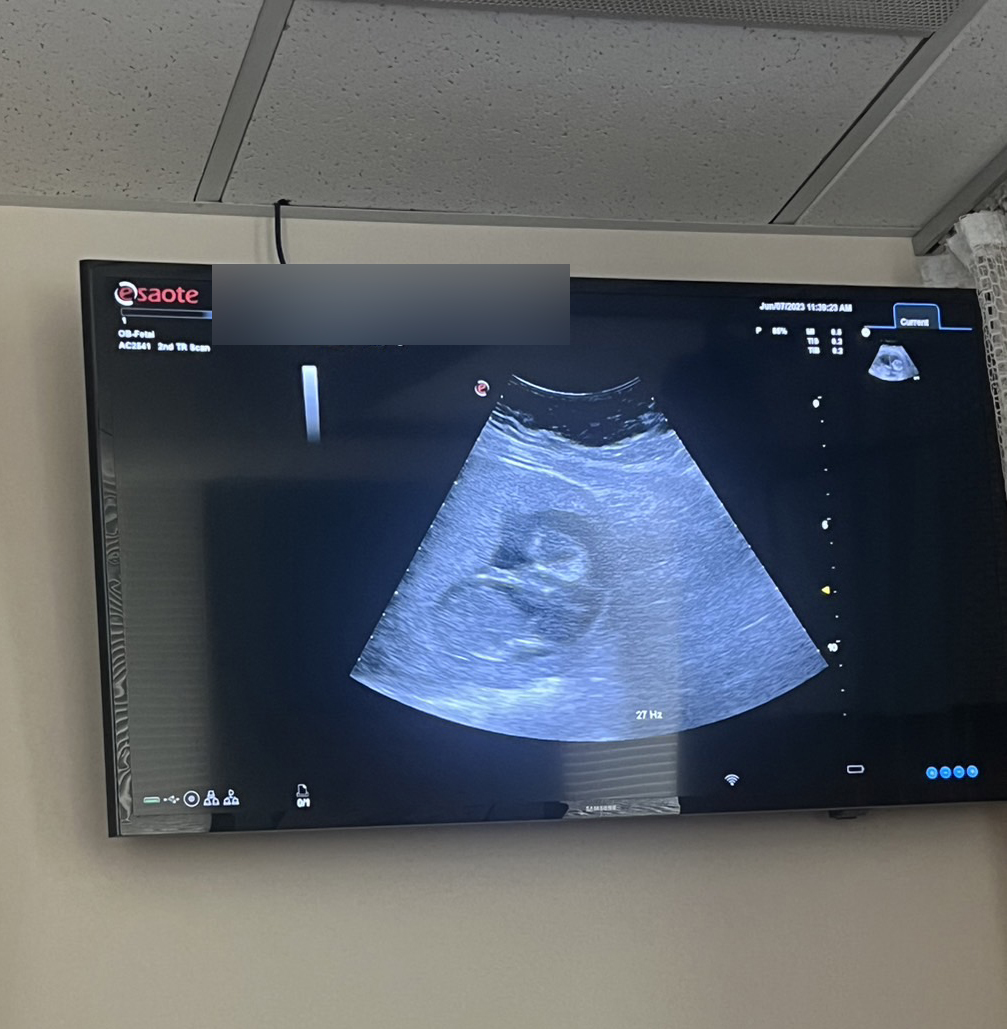

Return to 雙胞胎15週定期產檢! 👶👶